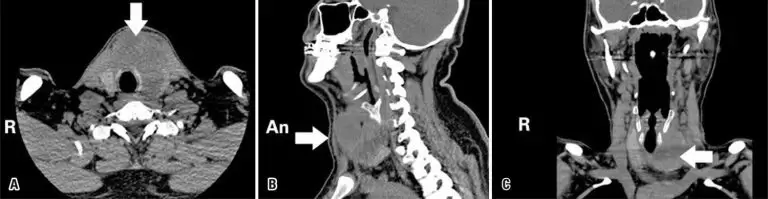

Acute suppurative thyroiditis is a very rare and life-threatening endocrine emergency. Thyrotoxicosis is a rare condition accompanying acute suppurative thyroiditis. While the majority of the cases in the literature are caused by different reasons, spontaneous development is very rare. We present a patient with acute suppurative thyroiditis who presented to our clinic with thyrotoxic findings, and we compared the case to the literature. A 31-year-old male patient was admitted to our clinic with a complaint of progressive neck pain, swelling and redness on midline neck, fever, and palpitations. On physical examination, swelling, redness and tenderness were detected on the neck region that was consistent with the thyroid location. He presented with tremor on the hands, tachycardia and agitation. Thyroid function tests were compatible with thyrotoxicosis, but there were findings supporting the presence of infection in biochemistry tests. On his radiological evaluations, a heterogeneous lesion divided with small septs was observed, with consolidation areas in the left thyroid lobe. In fine needle aspiration biopsy, 2mL of purulent fluid could be aspirated due to the presence of small, separated consolidation areas. He initiated on antibiotic therapy, propranolol, steroid and symptomatic treatment. Eikenella corrodens was detected on the culture antibiogram. Antibiotic therapy was continued for 14 days due to less symptoms and better biochemical values. After treatment, the patient had normal thyroid function, had relief of fever and redness of the neck, and was followed-up. It should be kept in mind that acute suppurative thyroiditis may develop spontaneously with the findings of thyrotoxicosis, with no risk factors.